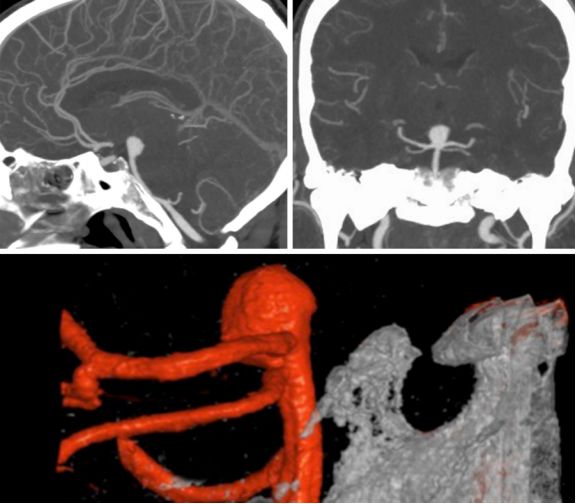

图1:图示一个典型的基底动脉分叉部动脉瘤(上排)。由于患者年轻,且动脉瘤解剖特征合适而进行显微手术夹闭。瘤颈到鞍背的高度对手术计划有重要参考意义(下图)。